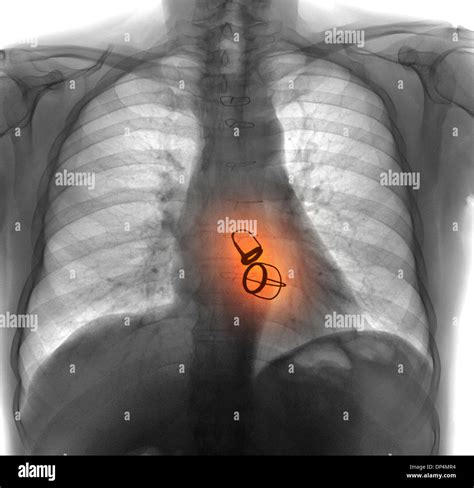

When the valve failure becomes severe and begins to impair heart function, surgery may be necessary. Modern medicine offers two main paths:

1. Valve Repair: This is generally the preferred approach. Surgeons reshape or reinforce the existing valve, which preserves the natural function of the heart.

2. Valve Replacement: If the valve is too damaged to repair, it is replaced with a mechanical or biological prosthetic valve.